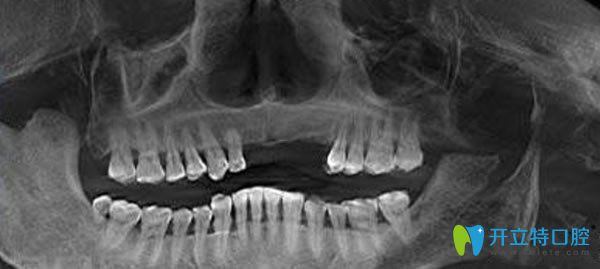

佳士潔口腔種植牙3D檢查圖片: